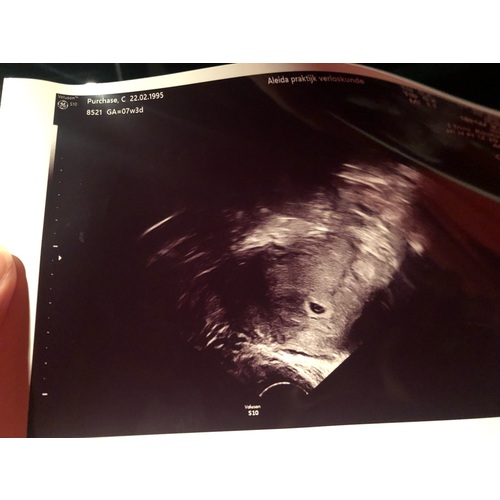

Hey hey wij hadden onze eerste echo met 7 weken althans dat dachten we! Er was niet heel veel te zien en ze meten maar 5+ weken met wel een kloppend hartje maar goed je maakt je toch wel druk want zelf kwam je op 7 weken uit. 2 weken later mochten we terug komen en toen was ik opeens 8 weken. Uit ei dalijk niet de 9e weken die we zelf dachten te zijn maar wel 8. En weer een kloppend hartje inmiddels zit ik op de 12 weken bijna 13 en is het altijd bij de zelfde datum gebleven al zou ik volgens mijn laatste menstruatie dus een week verder moeten zijn wss een late eisprong gehad. Wil zeggen dat het nog alle kanten op kan gaan zo vroeg in je zwangerschap niet te druk maken meis blijf genieten en houd het in je achter hoofd dan is de teleurstelling of juist geen teleurstelling dalijk wat minder hard. Blijf positief want het is gewoon heel moeilijk te meten zo vroeg! X

Dit moest dus een 5+ echo zijn maar was een 6+